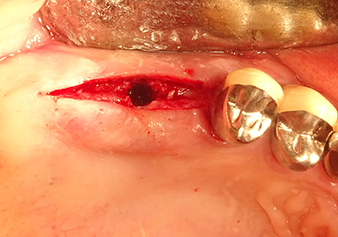

The Schneiderian membrane is carefully detached with the Z25P instrument (phase 1)

Fig.3: Following marking of the implant position and initial expansion of the bed, the Schneiderian membrane is carefully detached with the Z25P instrument (phase 1).

Following atraumatic preparation of the mucoperiosteal flap, the implant position was marked with the I1 instrument and the site prepared – until initial resistance was felt. Piezosurgical instruments were used in an up and down movement without any pressure being exerted. The piezoelectric vibration produced the desired and efficient cavitation.

The I2A instrument (diameter 2.0 mm) was then used to perforate the sinus floor intermittently and on the smallest scale possible. This special piezosurgical method ensures that the Schneiderian membrane is not damaged. When the Z25P was used, the membrane was already lifted slightly by the coolant supplied via the instrument tip (Fig. 3). The coolant quantity was just 50% in order to avoid high pressure in the implant bed.